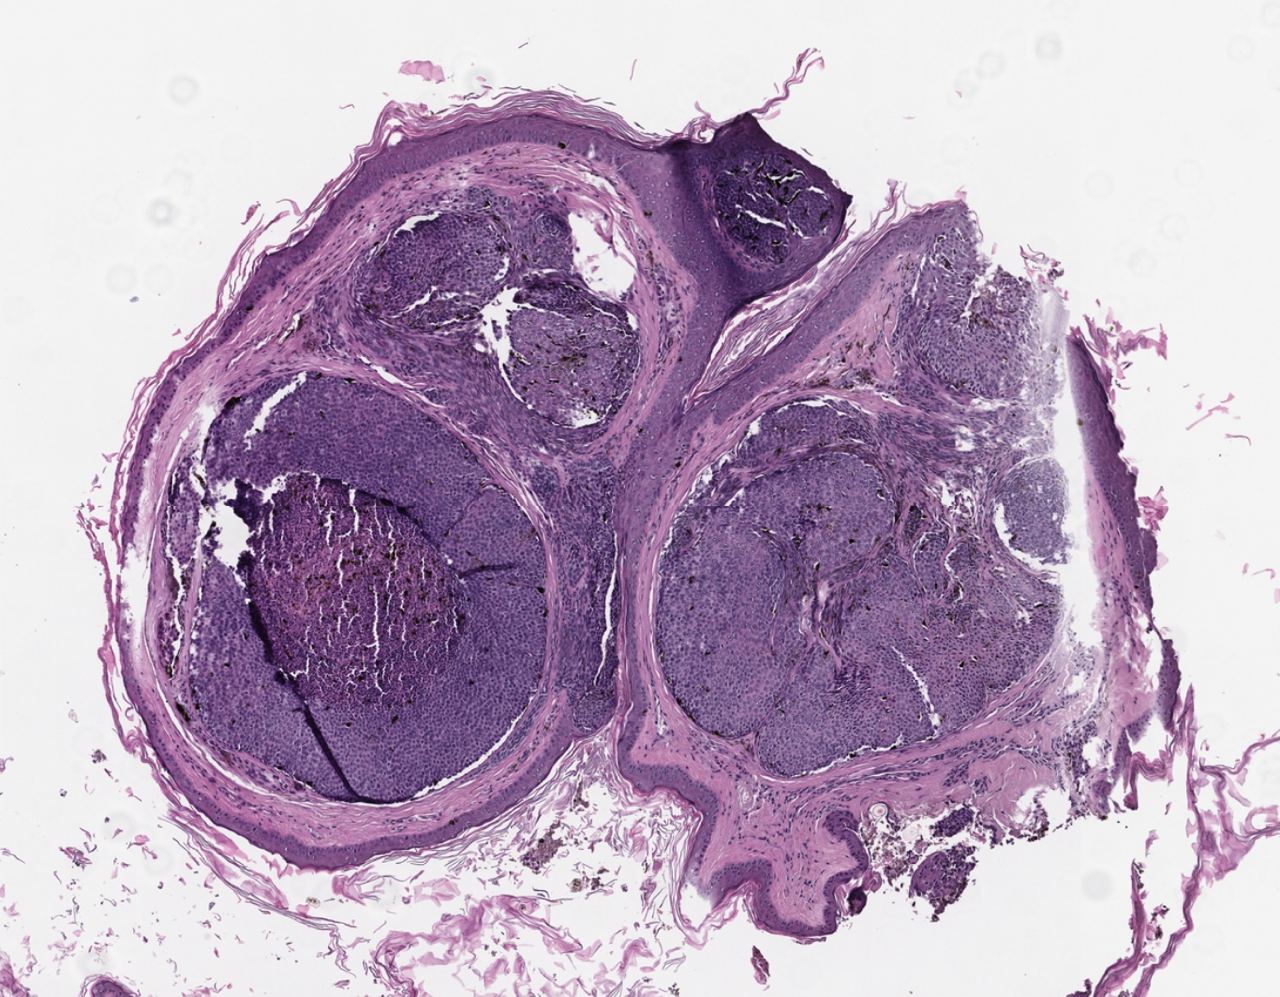

Базально - клеточная опухоль